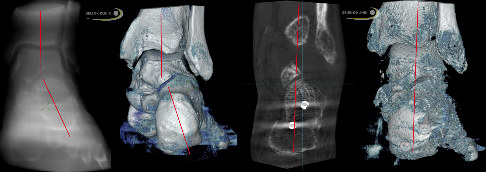

Rückfuß von hinten mit den Achsen in der CT (jeweils links) und im 3-D-Bild (jeweils rechts). Auf der linken Abbildung sieht man die deutliche Knickfuß-Fehlstellung mit verlagerten Achsen. Nach operativer Korrektur (rechtes Bild) erkennt man, dass die Ferse nach innen verschoben wurde und nun zentriert unter dem Sprunggelenk steht. Die Achsen sind gerade, verlaufen also korrekt axial von oben nach unten. © Gelenk-Klinik

Prinzipiell kann die Fersenbeinkorrektur bei jeder Art von Achsfehlstellung angewendet werden. Dies ist sowohl nach innen (Medialisierung) als auch nach außen (Lateralisierung) möglich. Beim erworbenen Knick-Senkfuß (Pes planovalgus) erfolgt die Korrektur nach innen (medial, deshalb medialisierende Verschiebeosteotomie). Dadurch wird die Knickfuß-(Valgus-)Fehlstellung ausgeglichen.

Indiziert ist die MDO insbesondere bei deutlicher Fehlstellung des Rückfußes, bei der das untere Sprunggelenk (Subtalargelenk) noch beweglich ist. Ist das Gelenk schon arthrotisch versteift, lässt sich die Rückfußfehlstellung durch die MDO nicht mehr korrigieren.